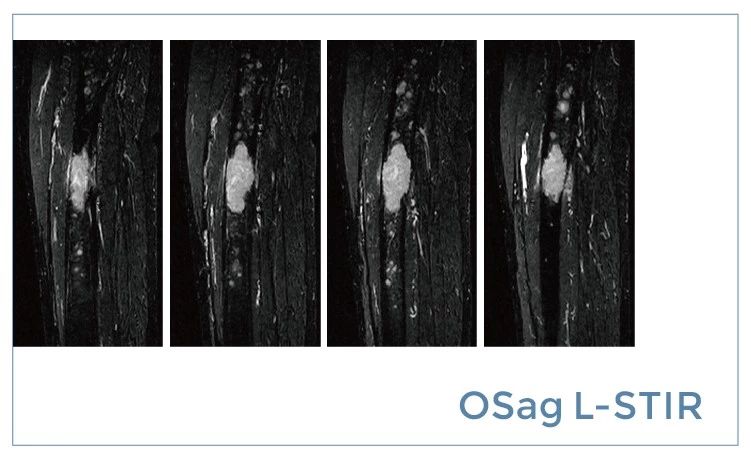

【朗润影像档案】20190712磁共振影像病例结果讨论